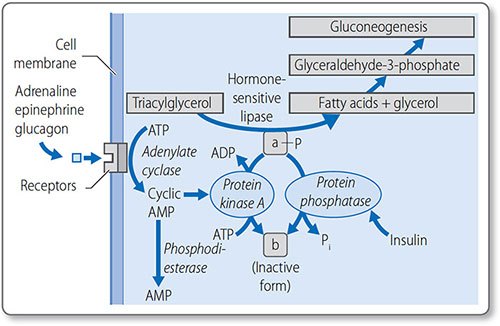

Regulation of lipolysis

Lipolysis is regulated through the control of lipase activity (Figure 1.42). Counter-regulatory hormones stimulate lipase when energy reserves are low: adrenaline (epinephrine), noradrenaline (norepinephrine), growth hormone, cortisol and glucagon. Conversely, insulin inhibits lipase.